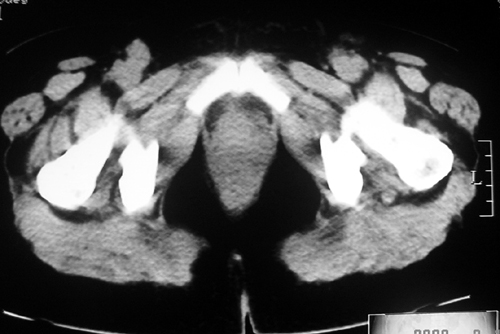

以下是引用余辉在2009-2-14 8:37:00的发言:[br]宫颈左后壁见较大低密度肿物影且向左后上方突出,宫腔内见大片状低密度区,考虑宫颈肿瘤,宫颈癌可能性大,伴宫腔积液或转移